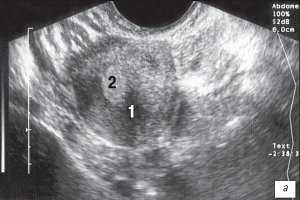

Выполненные нами исследования показали, что одной из основных особенностей однорогой матки являлось уменьшение ее ширины (рис. 1). Ее ширина колебалась от 3,4 до 4,2 см, составляя в среднем 3,8 см, в то время как в норме она варьировалась от 4,3 до 6,5 см при среднем ее значении 5,3 см.

Рис. 1. Ширина однорогой матки (3,4 см). Поперечное трансвагинальное сканирование.

1 - матка; 2 - эндометрий.